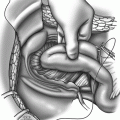

Rectocele

An anterior rectocele is evident on translabial ultrasound as a diverticulum of the anterior wall of the rectal ampulla into the vagina and generally is apparent only during the Valsalva maneuver (Fig. 28.3) and not at rest. Figure 28.4 shows a comparison of fluoroscopy and translabial ultrasound in a patient with a typical rectocele, contrasting appearances. Posterior rectoceles are uncommon in adult women and may be a form of intussusception rather than an actual rectocele (Fig. 28.5). A rectocele usually contains iso- to hyperechoic feces and often there is bowel gas as well, resulting in specular echoes and reverberations. Occasionally, there is no stool in the ampulla that could be propelled into the rectocele, and as a result it remains smaller and filled only with rectal mucosa. Because distension of a rectocele will depend on the presence and quality of stool, appearances may vary considerably from one day to the next. The severity of a rectocele can be quantified by measuring maximal descent relative to the inferior symphyseal margin and by determining the maximal depth of the sacculation (as seen in Fig. 28.4, which compares ultrasound and radiological findings in a patient with rectocele).